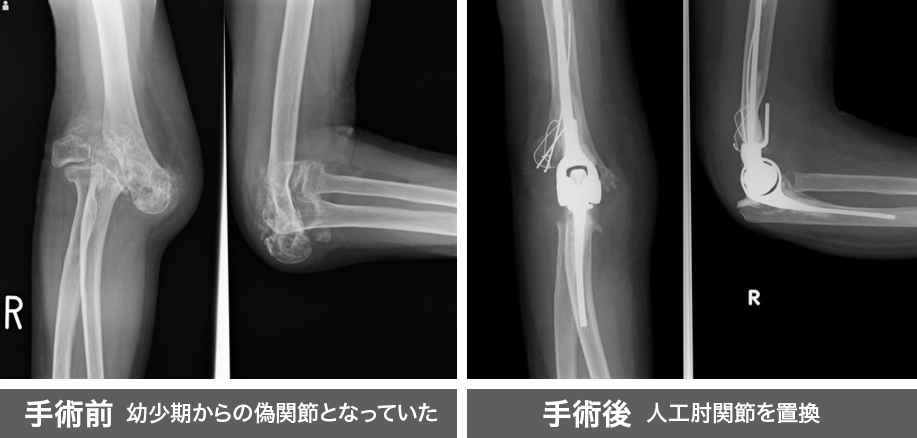

| 外傷 | 脱臼、骨折、肘関節不安定症、偽関節、上腕二頭筋遠位断裂、上腕三頭筋断裂 |

変形により痛みと手をついて立ち上がることが困難となっていました。

人工肘関節を挿入することで除痛を図りました。